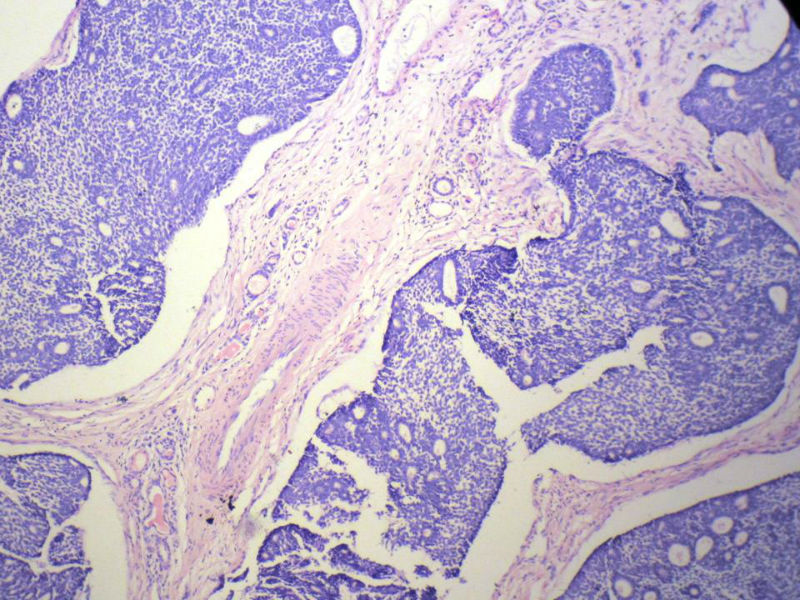

男,76岁,鼻塞两个月,CT提示左上颌窦占位,局部骨质破坏,口腔硬腭下降,局部活检。

左上颌窦占位图3

名称:图3

描述:幻灯片4

腺样囊性癌

腺样囊性癌,图像很典型的